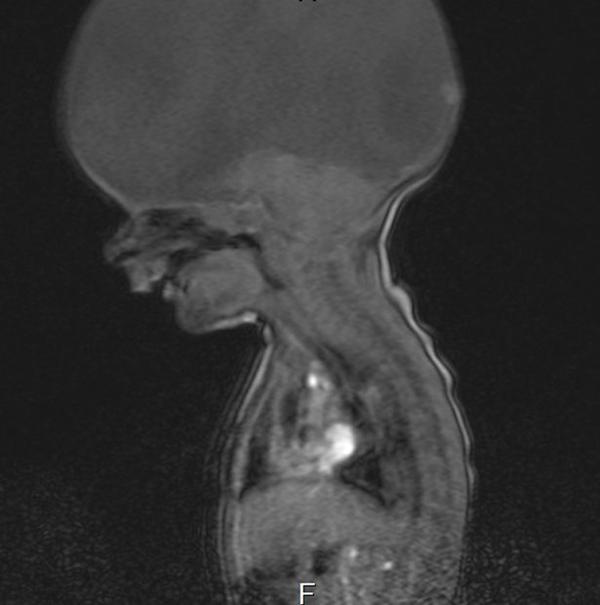

Trường hợp không não mà sống khỏe gần đây và nổi tiếng nhất là câu chuyện về cậu bé Aaron Murray, người Lanarkshire, Scotland. Bé sinh năm 2013 và bị bệnh Hydranencephaly bẩm sinh - chứng bệnh tương tự chứng não úng thủy, tức là gần như không có não mà chỉ có một phần rất nhỏ não được hình thành.

Đây là một căn bệnh cực hiếm ở trẻ và hầu hết những đứa bé sẽ chết trước khi sinh. Các bác sĩ đã từng tuyên bố Aaron chỉ có thể sống được vài phút hoặc vài giờ sau khi chào đời.

Phim chụp não của cậu bé Aaron khiến nhiều bác sĩ ngỡ ngàng khi không có não.

Tuy nhiên, phép màu đã xảy ra khi cậu bé vẫn thở tốt, sức khỏe ổn định dù thiếu đi bộ não. Sau 8 tuần quan sát và phẫu thuật để giảm tích tụ chất lỏng trong não, Aaron được cho về nhà nhưng các chuyên gia vẫn nghĩ em sẽ không qua khỏi.